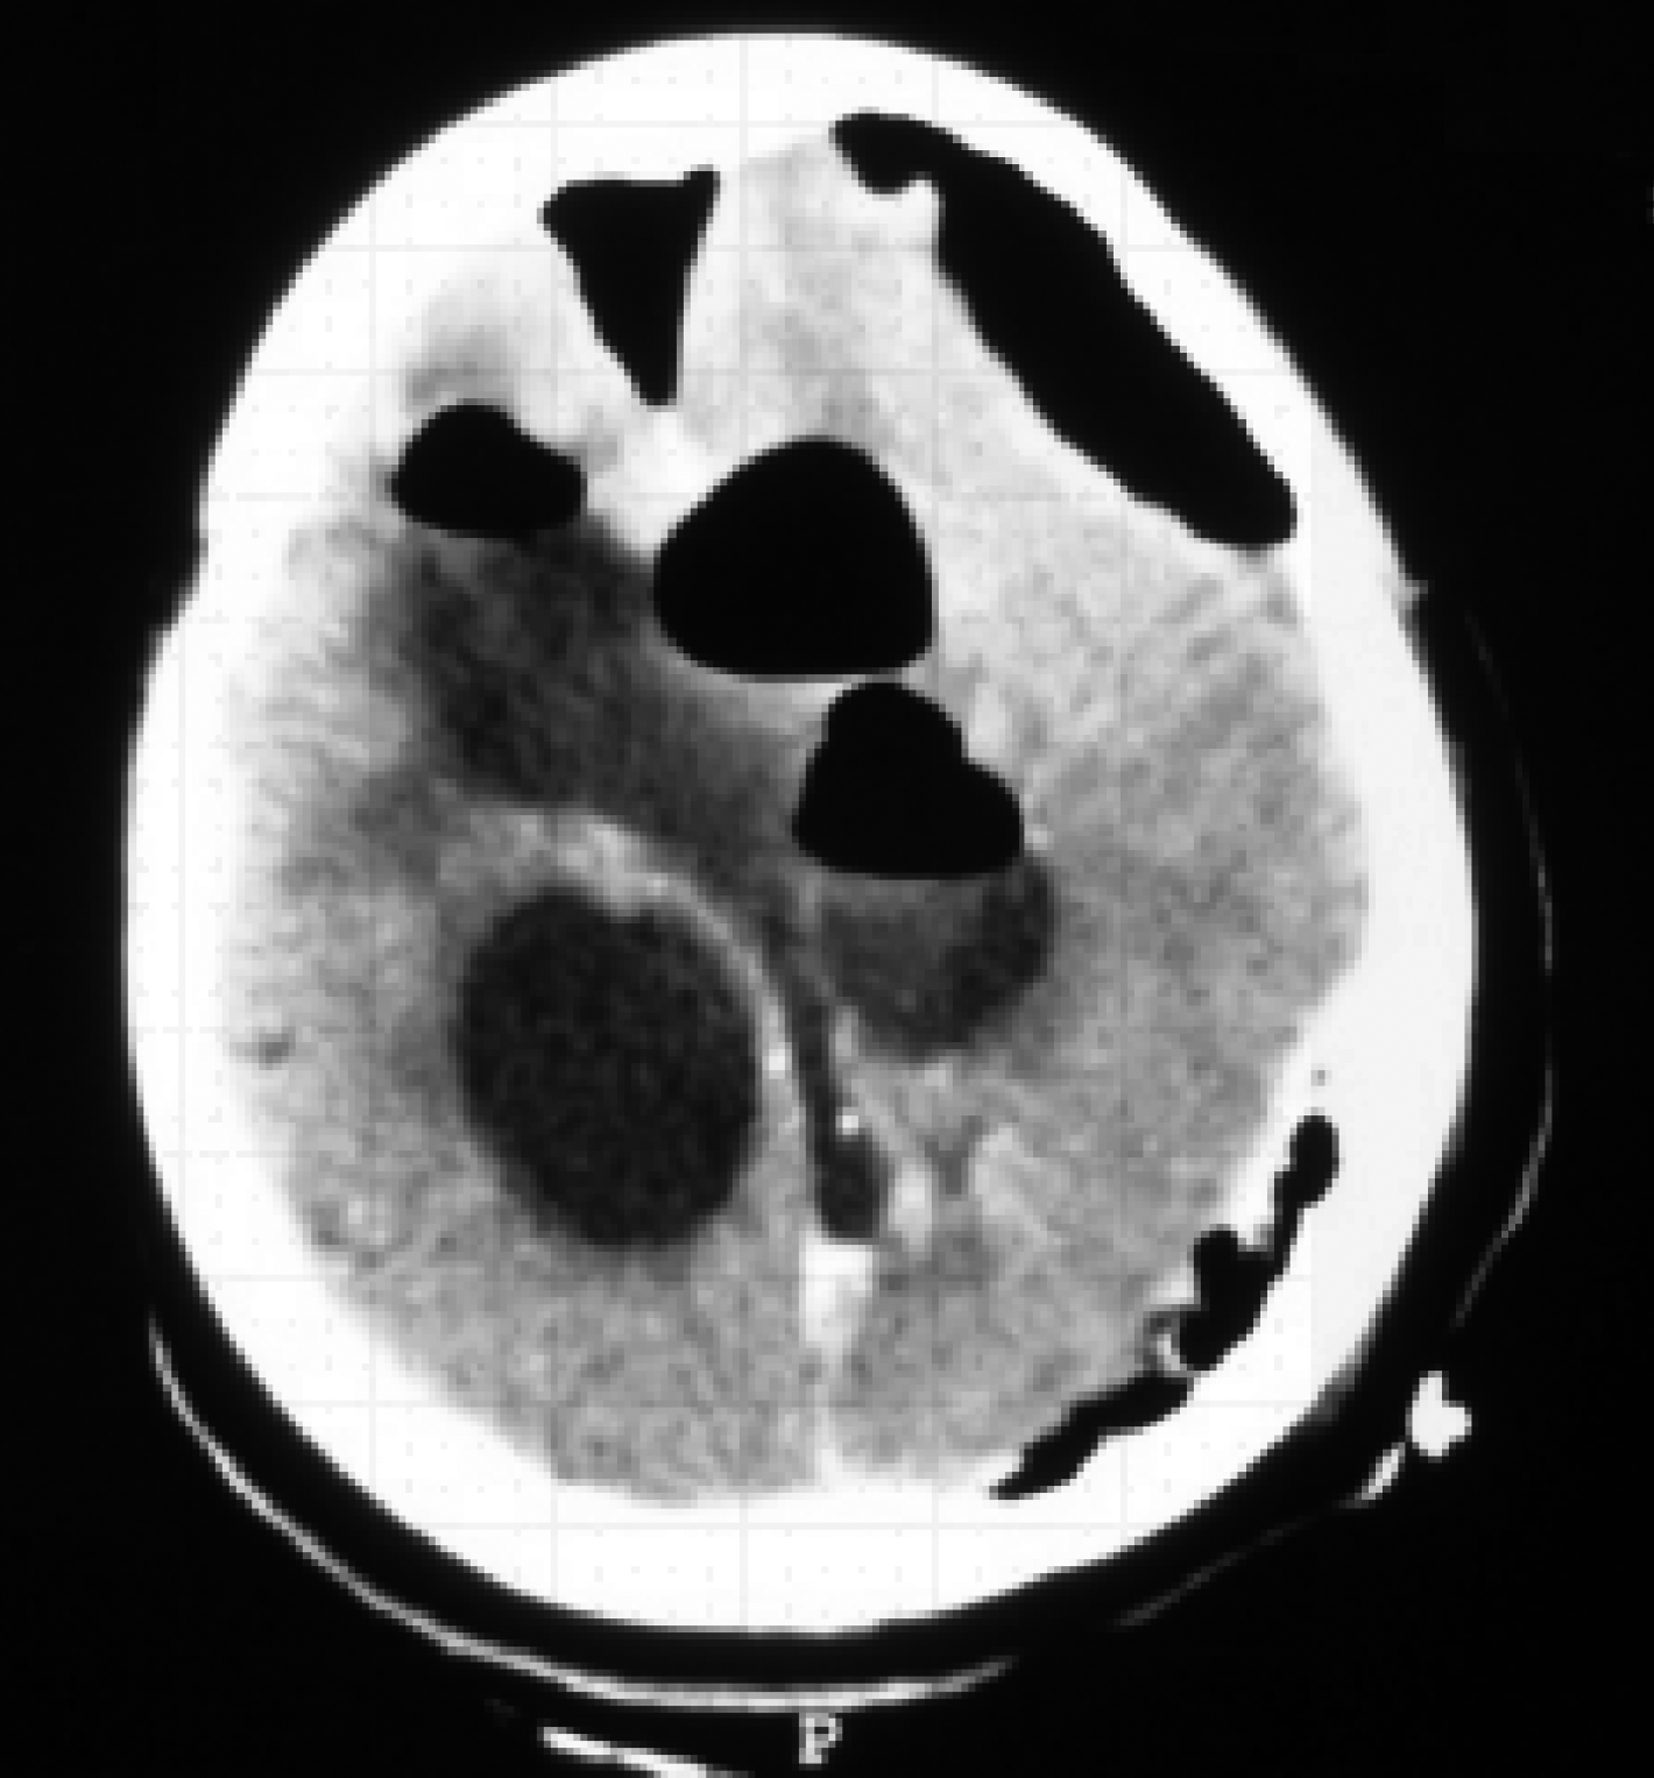

图3-1-1-1 出血后脑积水的脑室演变

a.发病时头颅CT:脑室内血肿呈高密度;b.发病12天后复查CT:血肿已呈低密度;c.发病5个月后头颅MRI:脑室明显扩张,脑室内未见异常信号;d.内镜下探查见脑室内仍有陈旧血斑及含铁血黄素沉积